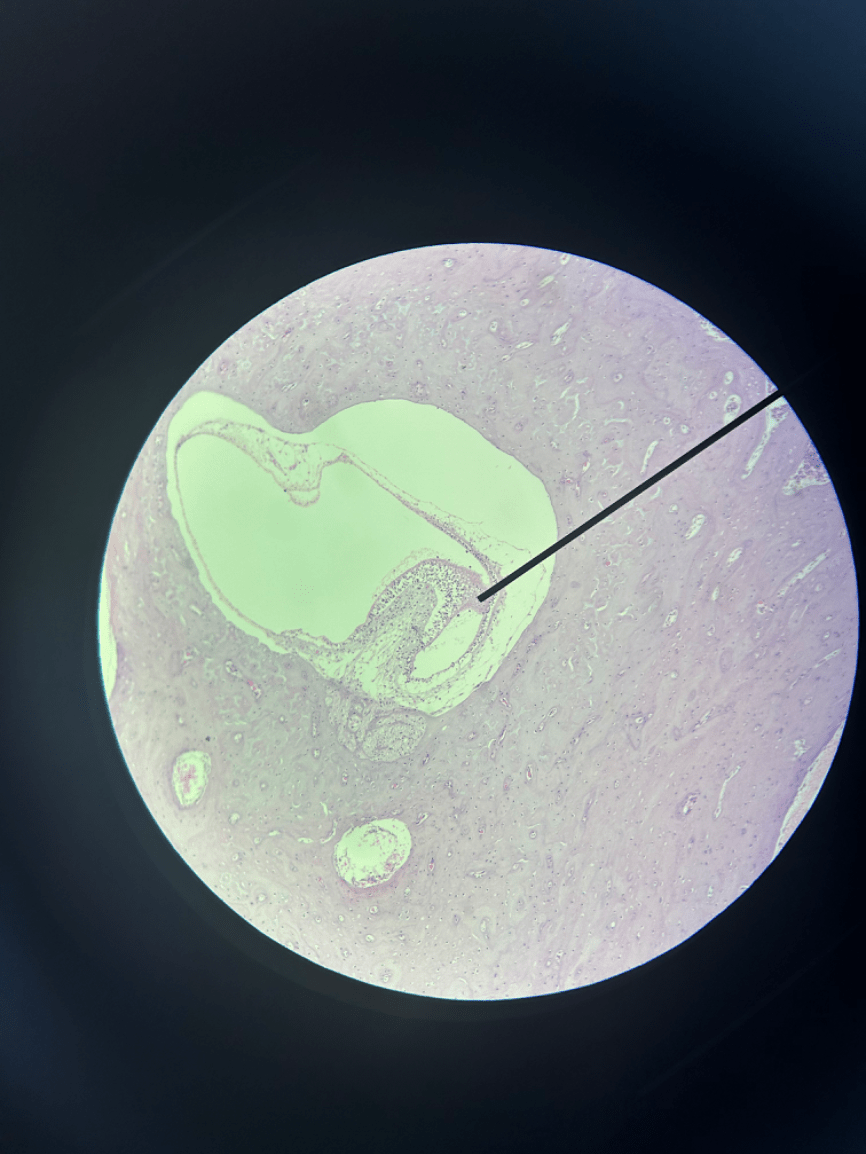

What organ is depicted in this slide and what cells are found in the appointed region?

The eye. Ganglionic cells can be found in this structure.